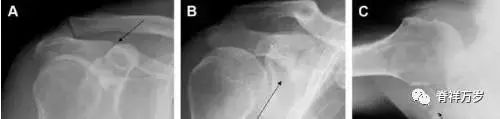

肩胛骨骨折

肩胛骨几何形状复杂,受到邻近其它骨性结重叠阻挡,且肩胛骨骨折少见,因此容易漏诊。当存在解剖变异时,诊断更为困难。

图 3 肩胛骨骨折正侧位片:由于骨块的叠加,(A)前后位片示「V」形高密度影(*),肩胛颈下方可见骨皮质碎片(箭头);(B)侧位片示骨皮质中断,骨折段移位,但由于肱骨的重叠遮挡,决断往往比较困难。